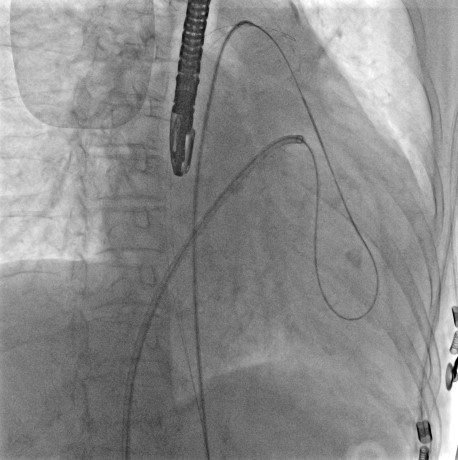

食道超声指导下经右侧股静脉入路穿刺房间隔,J型超滑导丝跨二尖瓣经左心室至升主动脉。使用圈套器将超滑导丝从右侧股动脉入路拉出,建立股静脉-右心房-左心房-二尖瓣-左心室-主动脉-股动脉动静脉轨道(图3)

图3. 建立动静脉轨道